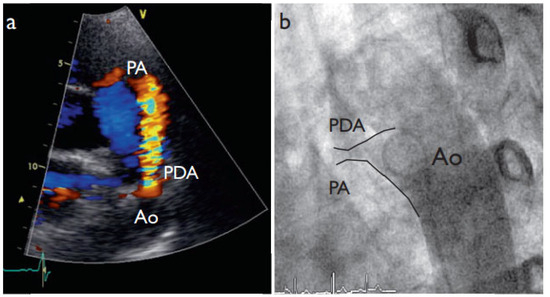

New Amplatzer Duct Occluder II for Antegrade Closure of Patent Ductus Arteriosus

by Stéphane Cook, Tobias Rutz and Bernhard Meier

Cardiovasc. Med. 2009, 12(11), 313; https://doi.org/10.4414/cvm.2009.01457 - 13 Nov 2009

Transcatheter closure of patent ductus arteriosus is a safe and effective technique. The new version of the Amplatzer PDA occluder (Amplatzer Duct Occluder II) permits antegrade delivery and significantly simplifies the procedure. Full article

Show Figures

Figure 1